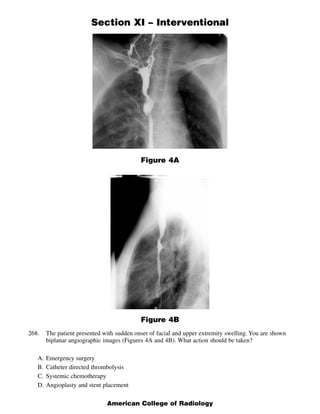

This document contains 5 clinical case scenarios involving interventional radiology procedures (questions 265-269). Each case is accompanied by an image and 4 possible answers. The correct answer is identified and a brief rationale is provided for each case. Question 270-279 continue testing knowledge of interventional radiology with additional multiple choice questions related to procedures, techniques, and disease processes.